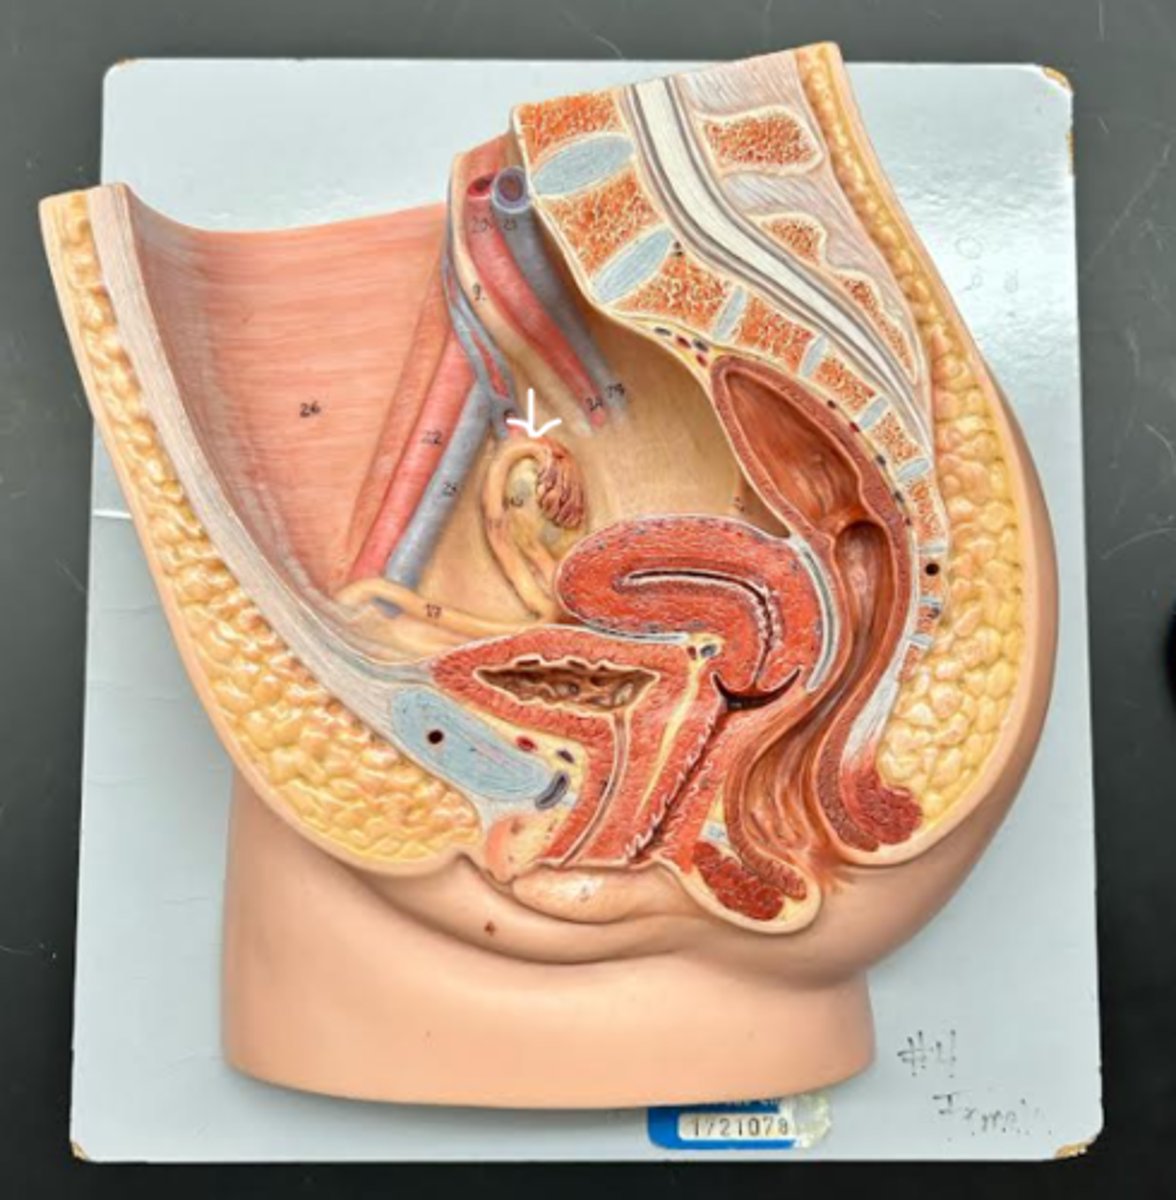

Vagina

Vaginal orifice

Hymen

Vaginal fornix

Ovary

Fallopian tube

Fimbriae

Infundibulum

Ampulla

Isthmus

Uterus

Fundus

Body of uterus

Cervix

Internal os

Cervical canal

External os

External urethral orifice